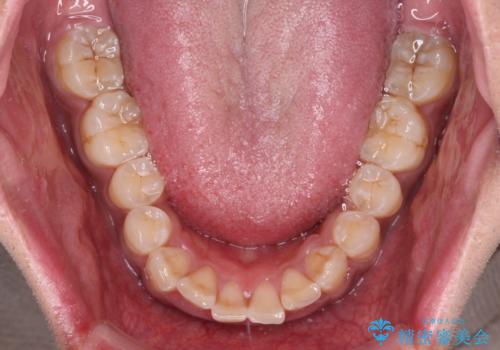

口元の突出感はあまりありませんでしたが、上顎歯列が全体的に前方にあり、更には下顎歯列が深く咬みこんでいるために、上顎前歯が前方に突出している状態でした。

抜歯は行わず、補助装置を用いて上顎歯列全体を後方移動させ、ワイヤー装置にて奥歯の咬み合わせを改善していくこととしました。

正面や横から見た印象が同じで用であっても、奥歯の咬み合わせが理想的であるかどうかによって、治療の難易度は大きく異なります。

こちらの方も難易度のやや高い状態で、2年以上の期間が予想されましたが、想定通りの2年強で治療を終えることができました。